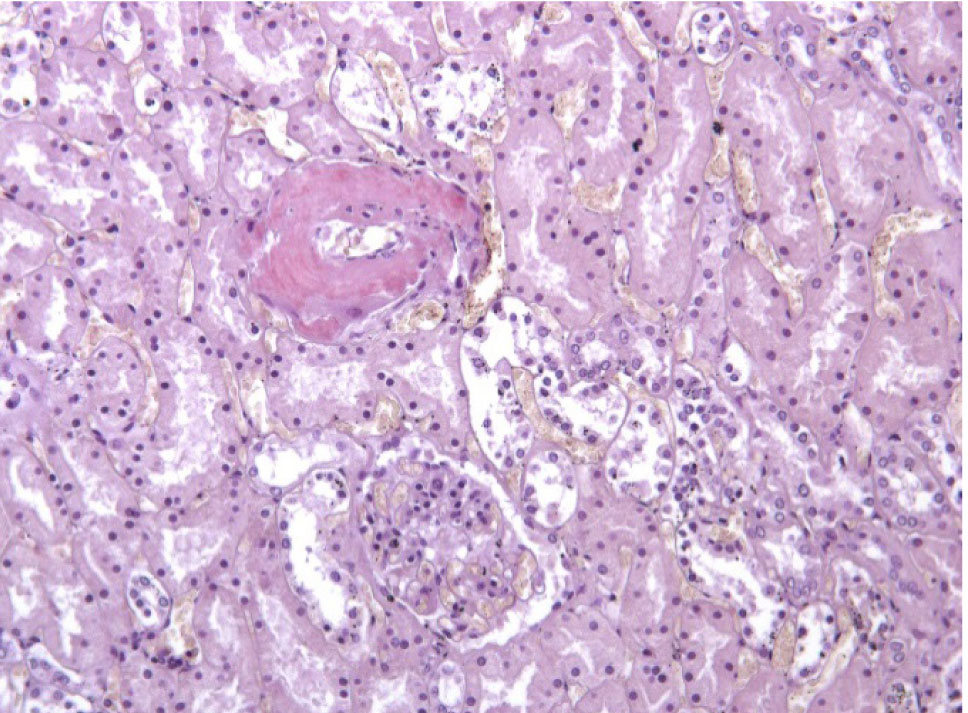

Почки – резкое уменьшение числа клубочков, отдельные полностью замещены однородной массой, дающей положительную реакцию на амилоид (рис. 3). В стенке сосудов также видны отложения амилоида (рис. 4).

Рис. 3. Почечный клубочек замещен амилоидными массами. Окраска конго красный, ×400